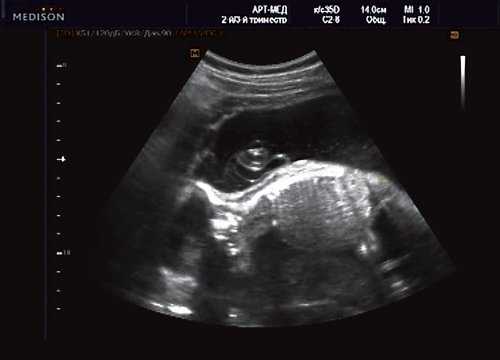

Клиническое наблюдение 4

Беременная 25 лет, обратилась в клинику в срок 18 нед. При эхографии выявлена грубая кифотическая деформация позвоночника в поясничном отделе (рис. 19).

Рис. 19. Деформация позвоночника.

В проекции деформации определяется миеломенингоцеле (рис. 20).

Рис. 20. Миеломенингоцеле.

Обнаружение типичных эхографических признаков позволило установить диагноз миеломенингоцеле.